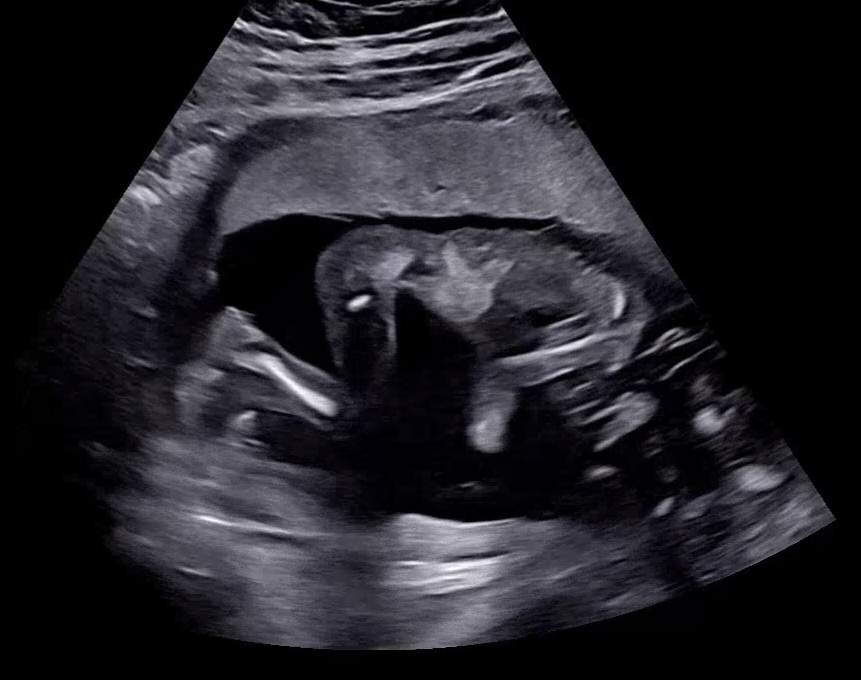

17주 이정도 크기 맞나요? (콩깍지주의🙈)

머리 크기는 18주에 가깝더라구요ㅋㅋㅋㅋㅋㅋㅋㅋ (엄빠 둘 다 머리가 크지는 않은데 왜...🥺) 오늘 머리랑 다리 위주로 많이 봤는데 다리가 유독 길어 보이는것이... 제 콩깍지에만 그리 느껴지는건가요?ㅋㅋㅋㅋ 아직 살이 붙기 전이라 말라서 그렇게 느껴지는건지...? 🥹 넘 궁금해서 네*버에 17주 초음파 검색해서 이미지 찾아보는데 다리가 선명하게 나온 사진이 별로 없더라구요ㅎㅎ 매번 곰돌이같이 동글동글 사진 봤던 기억이 아직 남아있어서 그런지 저래봐야 크기는 13cm 전후겠지만 엄청 크게 느껴지네용 ㅎㅎㅎㅎ

아~ 오른쪽이 머리구요. 왼쪽이 다리가 좌우반전 ㄴ자로 접힌거예요~ 아기가 오른쪽으로 엎드려있다구 보시면 됩니당^^